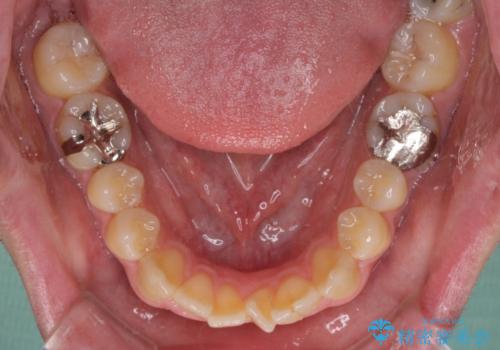

- 口がうまく閉じられないとのことで来院された患者様です。

上下唇をしっかり合わせようとすると、顎先が前方に突出してしまうほど口が閉じにくい状態でした。

口元の突出感を改善するために上下左右の第一小臼歯4本を抜歯し、ワイヤー装置にて矯正治療を行うこととしました。

また、上下前歯は舌の突出癖による開咬となっていたため、舌のトレーニングを徹底するよう指示しました。

舌突出癖の改善トレーニングは、仕上がり、治療期間、そして治療後の後戻りに大きな影響を及ぼします。

トレーニングをしっかりと行っていただいたため、スッキリとした口元に仕上がりました。